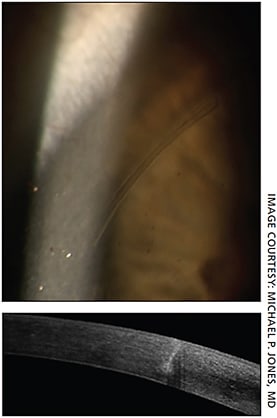

Using equipment like a Pentacam can have an additional benefit of not relying on an estimate of PCA and its effect on total corneal astigmatism — it will actually measure PCA directly. Using Pentacam PCA measurements with LENSAR femtosecond laser at the time of cataract surgery will allow the surgeon to perform arcuate incisions based on the PCA measurement. The downside of these devices is that they require equipment purchase, which may be out of reach for some practices.